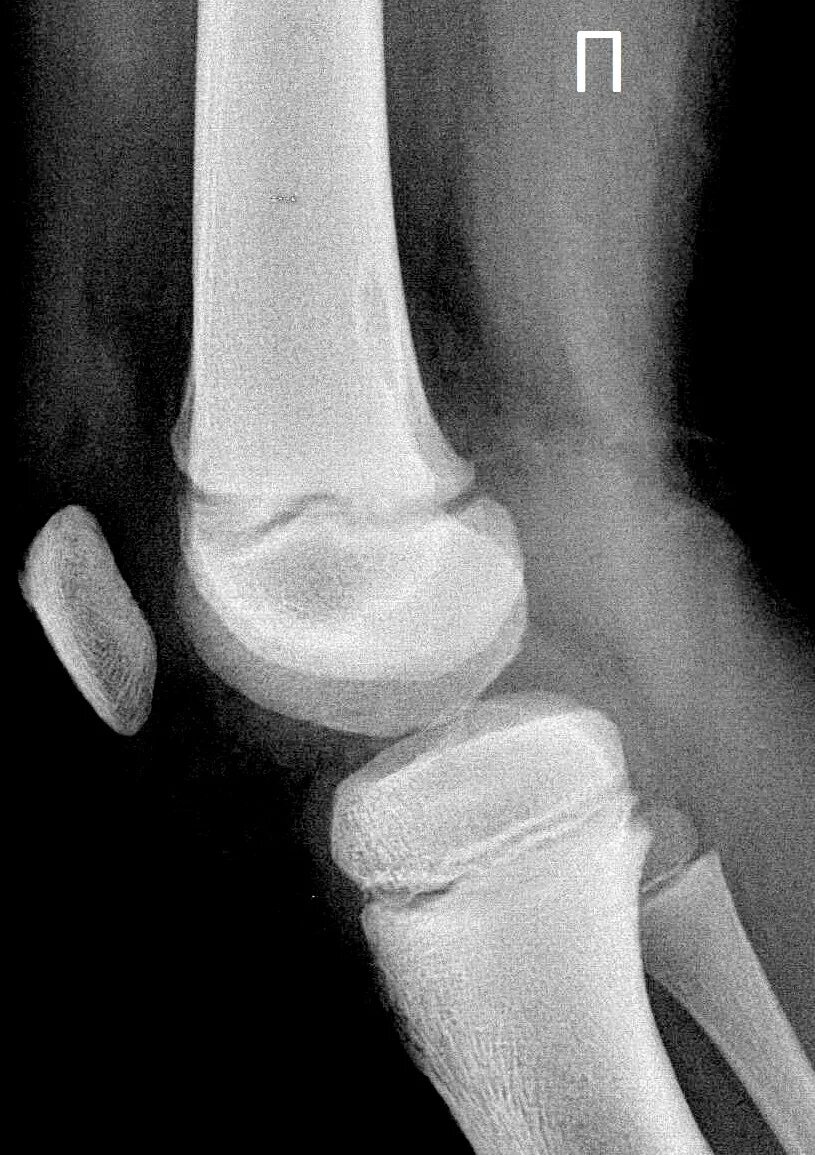

Код мкб шляттера